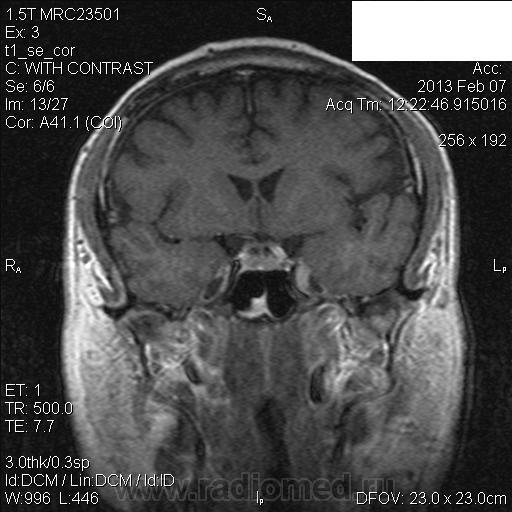

Здравствуйте! Уже писала сегодня сообщение по поводу последнего опубликованного Вами случая, но по каким-то причинам оно не отображается. Не складывается ли у Вас впечатление о наличии интрамуральной гематомы в кавернозном сегменте левой ВСА, с расширением наружного диаметра артерии и эксцентричным расположением просвета сосуда (диссекция). Не проводилась ли пациенту исследование интракраниальных артерий; с какими жалобами обратился пациент?

В анамнезе частые головные боли около года. Складывается впечатление, что зона патологических изменений прилежит к латеральной стенке кавернозного синуса, нерезко оттесняет прилежащие отделы левой ВСА. По поводу диссекции думала, но не видела в этом отделе, поэтому сомневаюсь. Исследование интракраниальных сосудов не проводилось.

Большое спасибо, Валентин Львович. Не знаю, стоит ли высказываться в пользу диссекции ВСА или больше данных за объемное образование?

Я бы в первую очередь подумала о диссекции.

А такое накопление контраста характерно для диссекции?

Здесь должна быть разная скрость накопления КВ, менингиома накапливает медленнее ( да и как-то не похоже на нее), можно сделать РКТ для установления гиперостоза матрикса( для исключения менингиомы) . При назначении аникоагулянтов должен быть эффект.

При контрастном усилении наблюдаются истинный и ложный поток. разделенные линейной полоской

Если все-таки думать о диссекции и об интрамуральной гематоме, то какой стадии трансформации крови это сответствует? Сигнальные характеристики не подходят ни острой, ни подострой, ни хронической стадии кровоизлияния.

Через 4 дня на томограммах по Т1 ВИ сохраняется изоинтенсивный МР-сигнал от загадочной зоны в области левого кавернозного синуса. Рекомендовала МСКТ-ангиографию. Если через неделю будет известен результат, то сообщу.

Если это диссекция ВСА, то почему она копит контраст? А вот кавернозный синус в принципе должен копить...